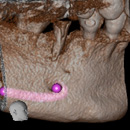

サイナスリフト

上顎の骨の上には上顎洞という大きな空洞があります。歯を失ってインプラントを埋めたい場合、上顎洞が大きく拡大していると、骨の厚さが不足し、インプラントの手術に必要な骨の厚みが得られないケースがあります。

このようなケースでは、上顎洞の膜全体を押し上げ、骨補てん材を用いて骨を作り、インプラントを埋入します。これが『サイナスリフト(上顎洞底挙上術)』です。

サイナスリフトを行った後、通常4~6ヶ月待って、骨が安定してからインプラント埋入を行います。